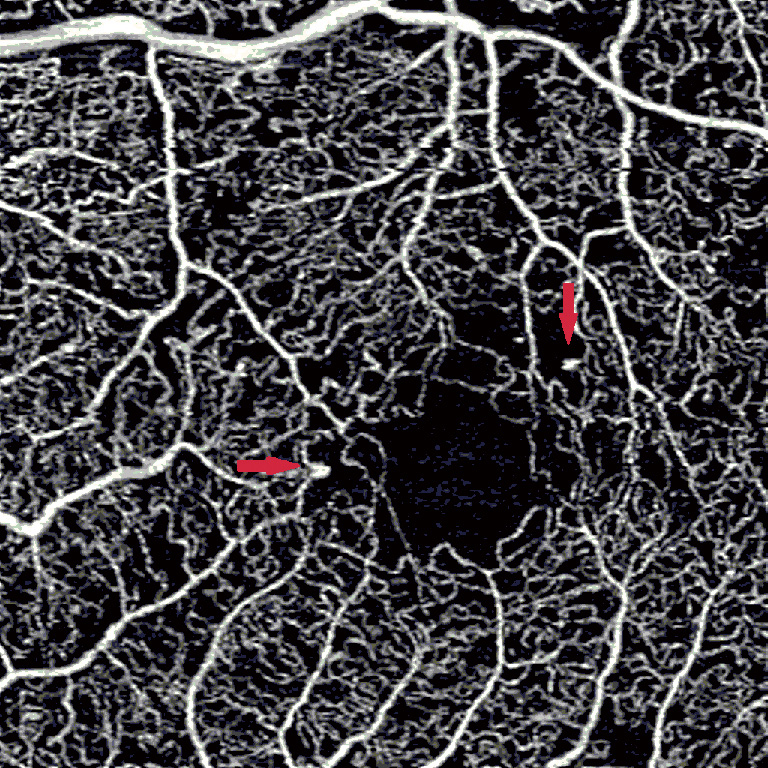

DME develops due to a combination of both VEGF-mediated and inflammatory factors, resulting in alterations in the blood-retinal barrier. The subsequent presence of fluid on OCT may interfere with imaging and segmentation capabilities. This occurs because of difficult automated identification of anatomical landmarks needed for correct segmentation (Figure 3) (20). Incorrect segmentation may affect OCTA images. DME has also been correlated with decreased OCTA signal intensity (9) as the cystoid spaces in DME often attenuate the reflected signal from deeper layers (21). Areas of DME may appear as flow voids on OCTA, areas that lack flow signal. It has been reported that these flow voids on OCTA were frequently larger than the cystoid spaces themselves, giving an inaccurate representation of actual morphology (Figure 4) (22). Studies have also determined the density of microaneurysms in superficial and deep retinal layers. Microaneurysms were found to be more frequent in the deep layer as compared to the superficial layer in eyes with DR. Their density in the deep layer further increases in eyes with DME. Additionally, a correlation between macular volume and the density of microaneurysms in the deep plexus has been demonstrated (23).

figure3

figure4